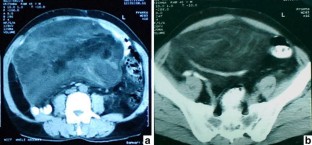

We describe the case of a middle-aged adult man with a well-differentiated liposarcoma of the mesentery. The patient presented with a recurrent tumor 5 years after the initial surgery. At recurrence, the histological features were those of a well-differentiated liposarcoma with focal osseous metaplasia without any evidence of dedifferentiation in the extensive sections examined.

Fig. 1